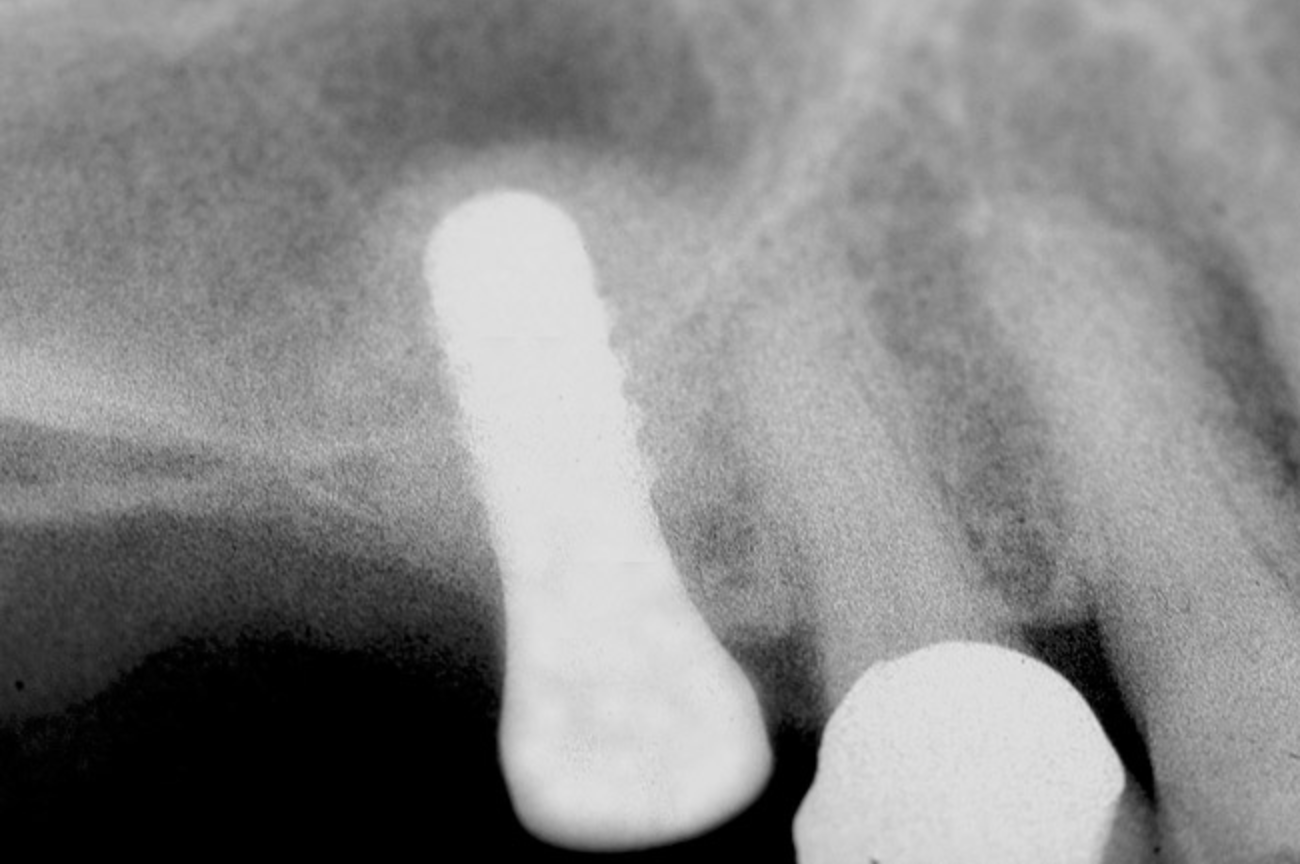

The 2-mm twist drill is used to create an osteotomy 1 mm short of the subantral floor. If any resistance is detected prior to reaching the 3-mm depth, drill penetration must be stopped, because the subantral cortical bone has possibly been reached. Any uncontrolled "push" would penetrate the bone and likely perforate the sinus membrane. A guide pin is then inserted and a radiograph taken to determine if drill penetration has terminated within 1 mm of the subantral floor (Figure 2). If the radiograph indicates that more than 1 mm of bone is present subantrally, the twist drill is used again to penetrate within 1 mm of the sinus floor. Alternately, an osteotomy tip for a piezosurgery unit can be used for this purpose. The final depth of penetration should be verified with another periapical film.

Figure 2  After drilling to a depth of 3 mm with a 2.1-mm twist drill, the guide pin was placed and a radiograph was taken to ascertain if the drill stopped within 1 mm of the subantral floor.

Figure 2